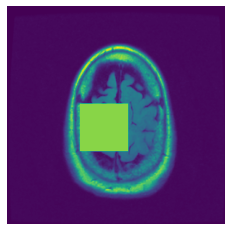

In figure 3, we present qualitative examples of different masking strategies. It is observed that, unlike context prediction and restoration, our method tends to propose targeted masks like the tumor regions or regions with abnormalities and avoids masking less helpful regions. However, it should be noted that Intelligent-Masking does not necessarily mask the tumor regions but considers all areas of interest that results in better feature learning. Examples of other masking samples are provided in supplementary materials. Furthermore, in medical images, unlike natural scenes, the structures are very local with imbalanced information throughout an image. Therefore, random masking strategies as shown in Fig 3 operate ineffectively by masking non-informative regions.

Figure 2: Qualitative examples of compared method’s strategies for masking

Figure 3: More qualitative examples of different distorting strategies including our method. We show the different self-supervised mechanisms on both datasets of MR (rows: 1-3) and ultrasound (rows: 4-6) images for lower-grade glioma and breast cancer diagnosis respectively. We include both images of normal (rows: 1,4) and cancer (rows: 2,3,5,6) conditions for each dataset. We also observe that our method treats each image based on its context information with no predetermined strategy.